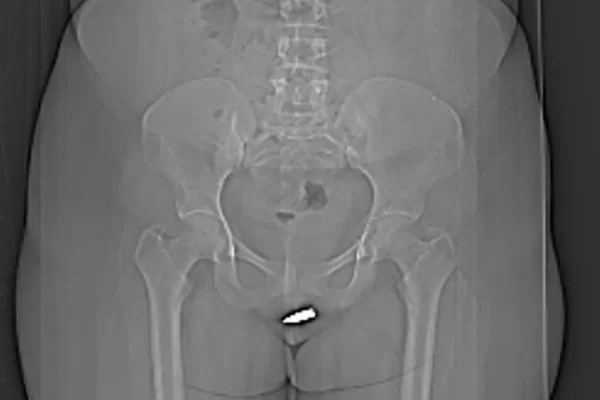

Uma mulher de 24 anos, da Somália, precisou passar por uma cirurgia de emergência para remover uma bala alojada em seu clitóris. Ela foi atingida acidentalmente enquanto estava em casa.

A jovem foi levada às pressas para o Hospital Erdoğan, na capital do país, queixando-se de fortes dores na vagina. Exames de tomografia computadorizada mostraram que o projétil de 2 centímetros atravessou a vulva da paciente e ficou alojado dentro do clitóris dela.

O projétil foi removido cirurgicamente sob anestesia local. Os médicos destacaram que o procedimento precisou ser feito com cuidado extra para não danificar a uretra e a região pélvica da paciente.

A jovem teve alta no dia seguinte, depois de uma avaliação médica constatar que ela não sofreu complicações devido à bala. Ela foi avaliada novamente um mês após a cirurgia, os médicos disseram que estava assintomática e sem intercorrências.